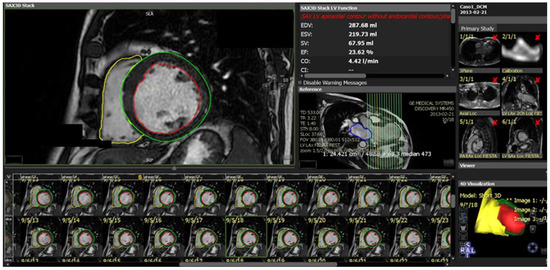

Figure 7.

Image segmentation platform. Functional and volume analysis to obtain ejection fraction, volumes, stroke volume, cardiac index, and left ventricle mass in end diastolic phase. Green: epicardial contour; red: endocardial contour; yellow: right ventricle. EDV—end diastolic volume; ESV—end systolic volume; SV—stroke volume; EF—ejection fraction; CO—cardiac output; CI—cardiac index.